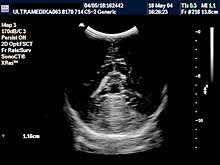

C) UZ dijagnostika kukova

Ultrazvnučni pregled kukova je neophodan u

prvom mesecu života.

Napomena:

Ovaj neinvazivni pregled omogućava tačnu procenu nezrelosti

ili iščašenja kuka i obično je dovoljno informativan za određivanje

načina lečenja. Dalja procena rasta kuka je takođe u domenu UZ

dijagnostike. Nema potrebe naglašavati da se deca rađaju sa

oboljenjima kukova koji se ne moraju obavezno kliničkim pregledom

prepoznati. Najvažniji preduslov za adekvatno lečenje nezrelosti

kukova je što ranije postavljena dijagnoza (inače dijagnoza nezrelosti

kukova je moguća u toku UZ pregleda trudnoće). Jedini razlog za

odlaganje pregleda je posedovanje neadekvatne ultrazvučne opreme.Primenjena tehnika: 2D broad band, program za automatsko izračunavanje

stepena nezrelosti po Grafu. Ultrazvučna sonda od 5-12 MHz(megaherca)